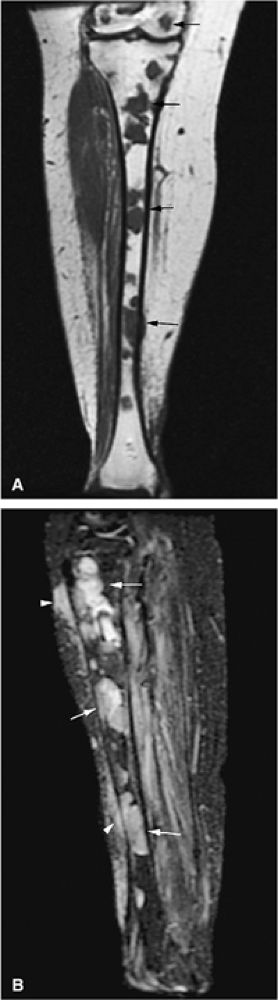

![]() |

FIGURE 13.12 ● Abnormal low-signal-intensity marrow of the bilateral lower extremities due to leukemic infiltration, seen on a coronal T1-weighted image. Note extension of leukemic infiltrates into the epiphyses.